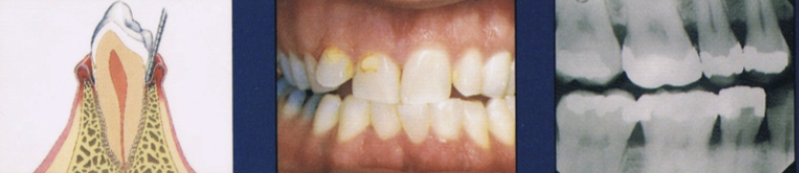

Describe moderate stage of periodontal disease

More advanced stage of previous condition

Increased destruction of periodontal structures

Noticeable bone loss, support, and increase in mobility

Furcation involvement